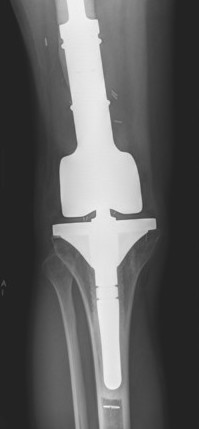

Management

Algorithm

1. Neoadjuvent chemotherapy

2. Restage

3. Surgical resection

4. Chemotherapy

5. Radiotherapy - if margins inadequate

Wide Resection - limb salvage / amputation

2 cm margin of normal tissue if able